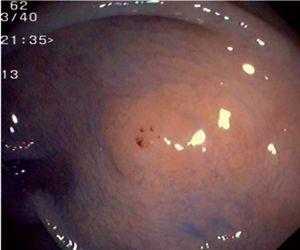

Fig. 3. Examples of flat lesions with conventional examination and after the application of indigo carmine 0.2-0.5%. a, b) Small flat adenoma, 3 mm in size. c, d) Large flat adenoma, 15 mm in size. e, f) Completely flat lesion (IIb in the Japanese classification). g, h) Depressed lesion, 3 mm in size) (IIc in the Japanese classification). I, J) Depressed lesion, 7 mm in size, histopathological study revealed submucosally invasive cancer (traditionally IIc in the Japanese classification, although recently such depressed lesions with a distinct central protrusion indicating submucosal invasion are termed IIc + Is). k, l) Flat elevated lesion with central depression, 10 mm in size, corresponding to a submucosally invasive cancer (IIa + IIc in the Japanese classification).